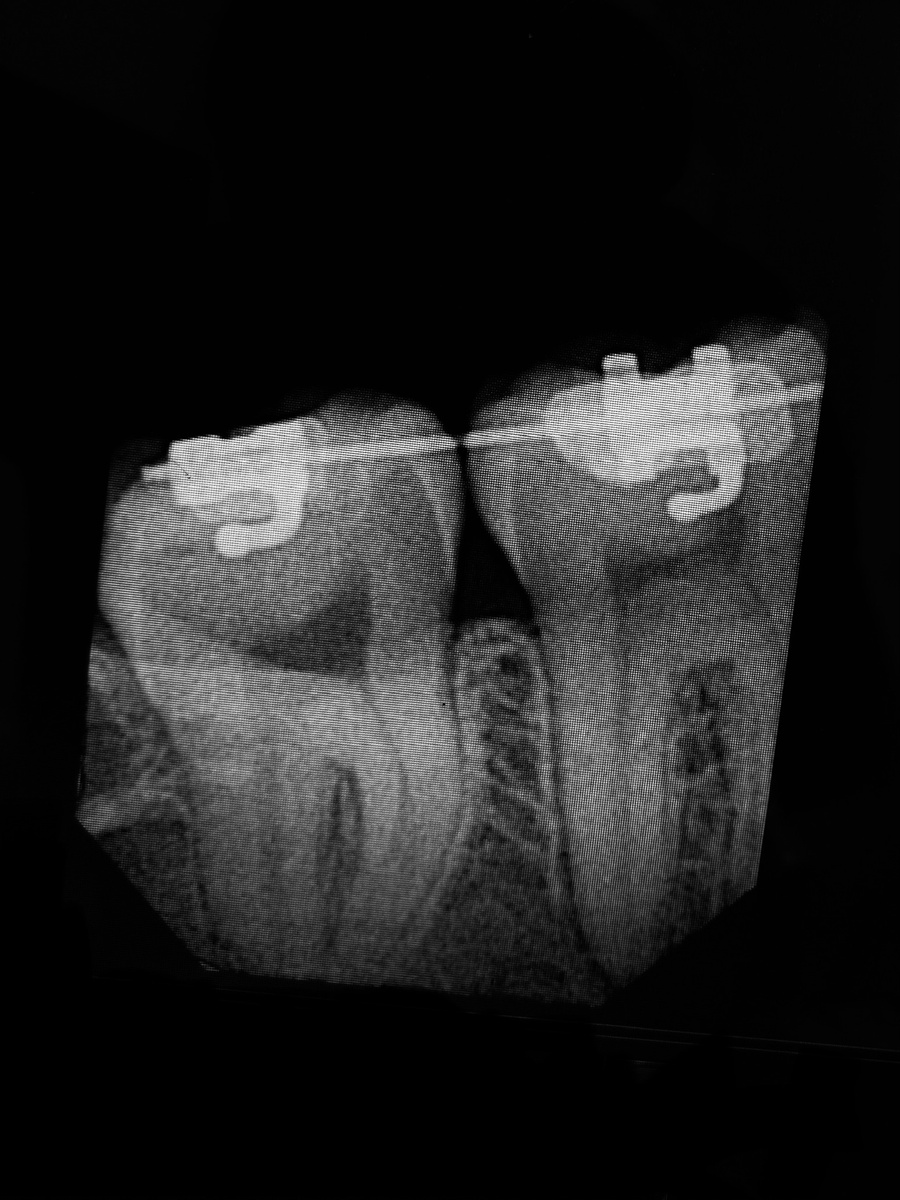

Рентгеновский снимок зубов

Так же и наши драгоценные зубы имеют нервы, кровеносные и лимфатические сосуды.

Вот вам и простое доказательство.